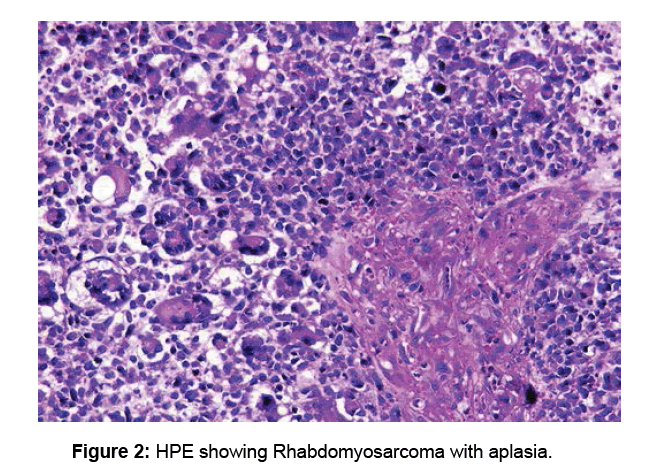

A Case Of Rhabdomyosarcoma Of The Sino Nasal Tract In An Adult Male: A

www.omicsonline.org

www.omicsonline.org

rhabdomyosarcoma case tract literature sino nasal male adult report review rare aplasia hpe showing figure